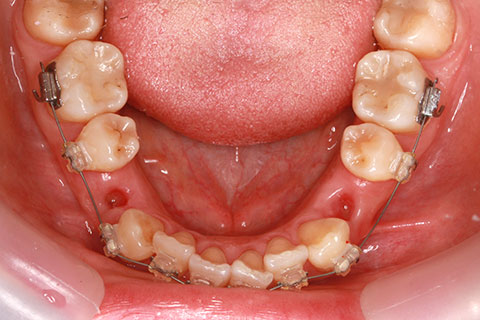

矯正期間18ヶ月

フルリンガル矯正2(上下の歯を舌側矯正で治療)

治療前

治療中

治療後

- 年齢・性別

- 42歳男性

- 治療期間

- 1年6ヶ月

- 抜歯

- なし

- 治療費

- 120万円(税込み)

- 備考

- マルチブラケットを用いた矯正治療

- 治療内容

- 反対咬合をフルリンガル矯正治療にて改善

- 施術の副作用(リスク)

- 表側矯正と比較して、歯根の角度を確立する「トルク」の力がかかりにくい。